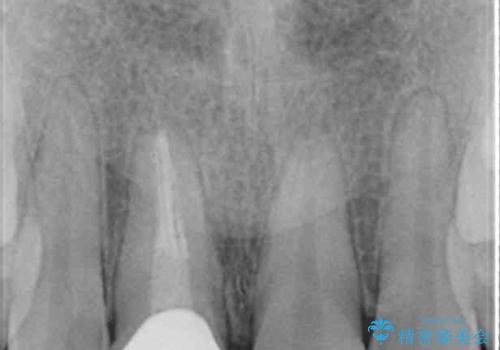

レントゲン写真より、歯根の炎症が認められなかったため、ファイバーコアによる土台築製後、オーダーメイドタイプのオールセラミッククラウンにて補綴することとしました。